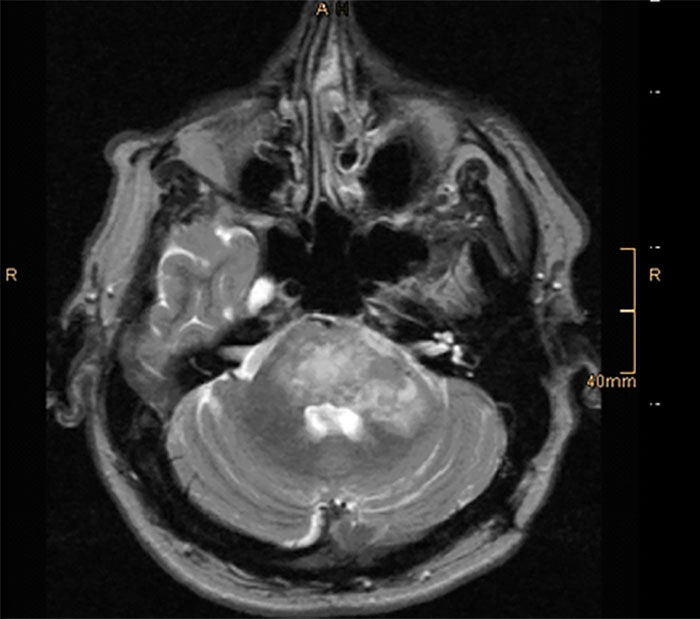

One guy who had been stabbed through the heart with a steak knife by his wife was in peak physical shape, but when the pathologist pulled his brain out he said "look at this". I have no biology training, but the golf ball sized tumor on his brainstem was obvious even to me. Doctor said he had maybe 90 days to live at the time of his death.